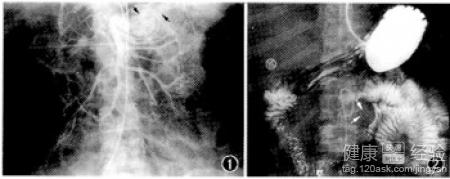

中風是什麼?腦卒中(Stroke)是腦中風的學名,是一種突然起病的腦血液循環障礙性疾病。又叫腦血管意外。是指在腦血管疾病的病人,因各種誘發因素引起腦內動脈狹窄,閉塞或破裂,而造成急性腦血液循環障礙,臨床上表現為一過性或永久性腦功能障礙的症狀和體征。腦卒中分為缺血性腦卒中和出血性腦卒中。